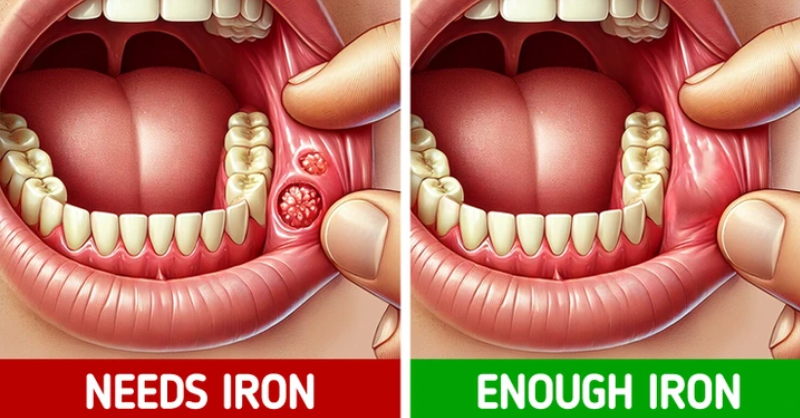

7 Signs Your Body Uses to Tell You What It Needs

Our body is a complex system where everything is interconnected. When something isn’t working properly, it often sends signals through different parts of the body. Recognizing these signs...